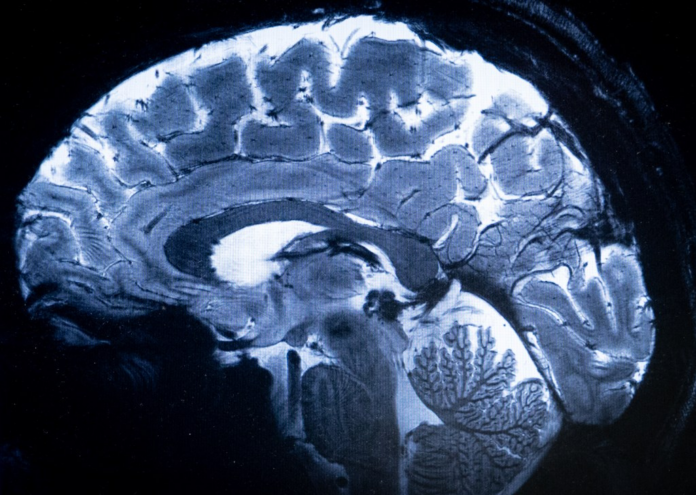

A week ago today, a gunman identified as Shane… [4695 chars]